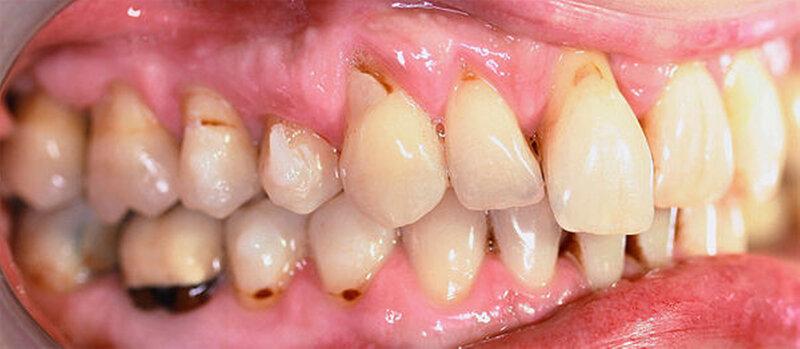

Anamnestisch lagen keine Besonderheiten vor. Es ist jedoch zu vermerken, dass ein regelmäßiger Alkohol-, Koffein- und Nikotinkonsum zugrunde lag. Intraoral zeigte sich ein bereits konservierend versorgtes permanentes Gebiss mit aktivem und inaktivem kariösen Geschehen. Große Anteile der Zahnhälse lagen nach Zahnfleischrückgang in Kombination mit Knocheneinbrüchen frei. Zahn 27 wurde bereits extrahiert.

Kieferorthopädisch imponierte beidseits eine neutrale Verzahnung bei einem tiefen Biss von 5 mm – bedingt durch die Verlängerung beider Frontzahngruppen. Besonders Zahn 11 zeigte eine erhebliche Verlängerung und Protrusion mit einer sagittalen Frontzahnstufe von 5 mm. Sowohl die Frontzähne im Ober- als auch im Unterkiefer wiesen eine lückige Beziehung zueinander auf (Abbildung 1).